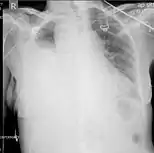

Chest MRI showing a hemothorax in a 16-day-old infant

Magnetic resonance imaging (MRI) can be used to differentiate between a hemothorax and other forms of pleural effusion, and can suggest how long the hemothorax has been present for. Fresh blood can be seen as a fluid with low T1 but high T2 signals, while blood that has been present for more than a few hours displays both low T1 and T2 signals.[27] MRI is used infrequently in the trauma setting due to the prolonged time required to perform an MRI, and the deterioration in image quality that occurs with motion.[22]